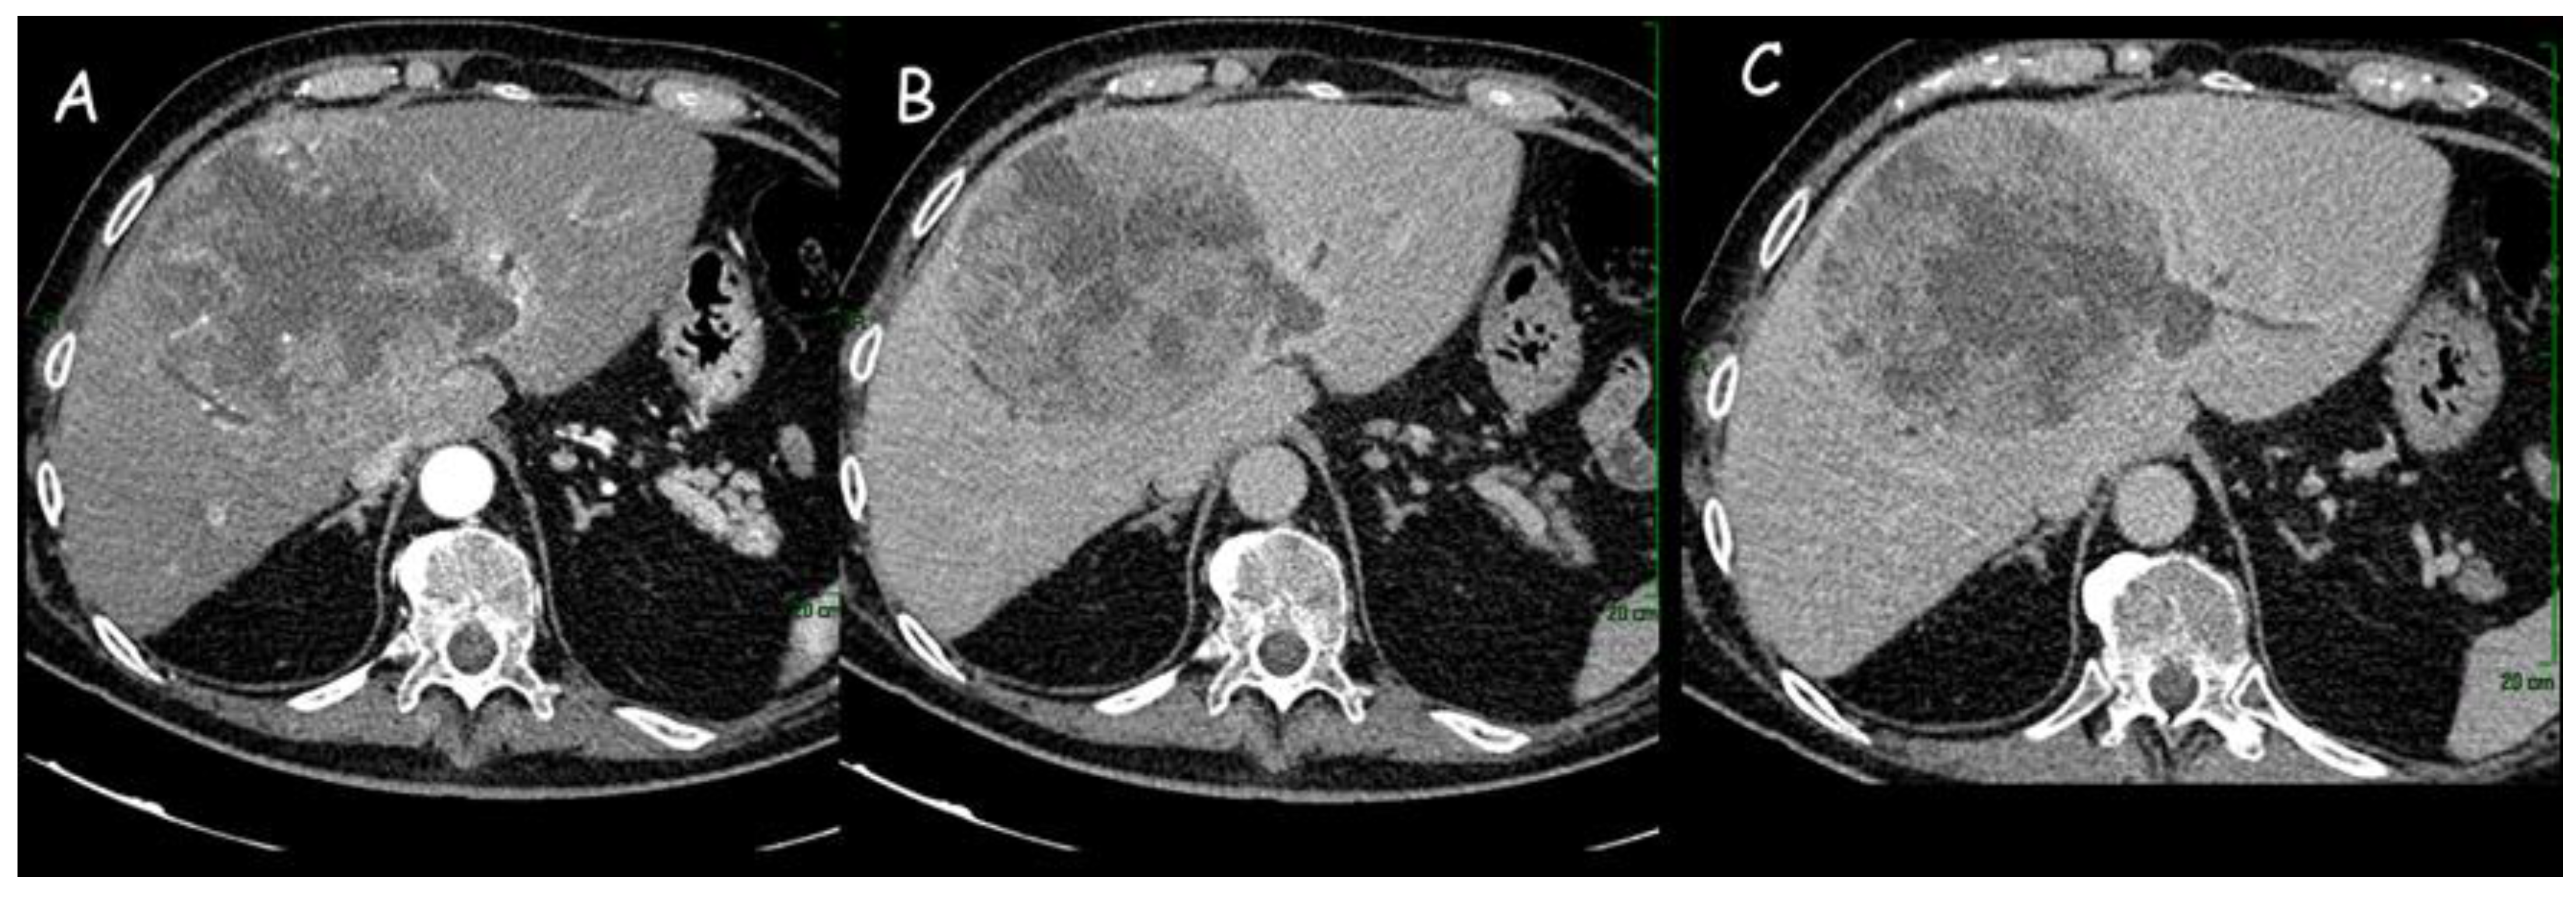

1.1. Computed Tomography

- Kim, S.A.; Lee, J.M.; Lee, K.B.; Kim, S.H.; Yoon, S.H.; Han, J.K.; Choi, B.I. Intrahepatic Mass-forming Cholangiocarcinomas: Enhancement Patterns at Multiphasic CT, with Special Emphasis on Arterial Enhancement Pattern—Correlation with Clinicopathologic Findings. Radiology 2011, 260, 148–157. [Google Scholar] [CrossRef]

- Park, H.M.; Jang, H.Y.; Lee, D.E.; Kang, M.J.; Han, S.-S.; Kim, S.-W.; Park, S.-J. Prognostic impact of tumor vascularity on CT in resectable intrahepatic cholangiocarcinoma. HPB 2022, 24, 359–369. [Google Scholar] [CrossRef]

- Ciresa, M.; De Gaetano, A.M.; Pompili, M.; Saviano, A.; Infante, A.; Montagna, M.; Guerra, A.; Giuga, M.; Vellone, M.; Ardito, F.; et al. Enhancement patterns of intrahepatic mass-forming cholangiocarcinoma at multiphasic computed tomography and magnetic resonance imaging and correlation with clinicopathologic features. Eur. Rev. Med. Pharmacol. Sci. 2015, 19, 2786–2797. [Google Scholar]